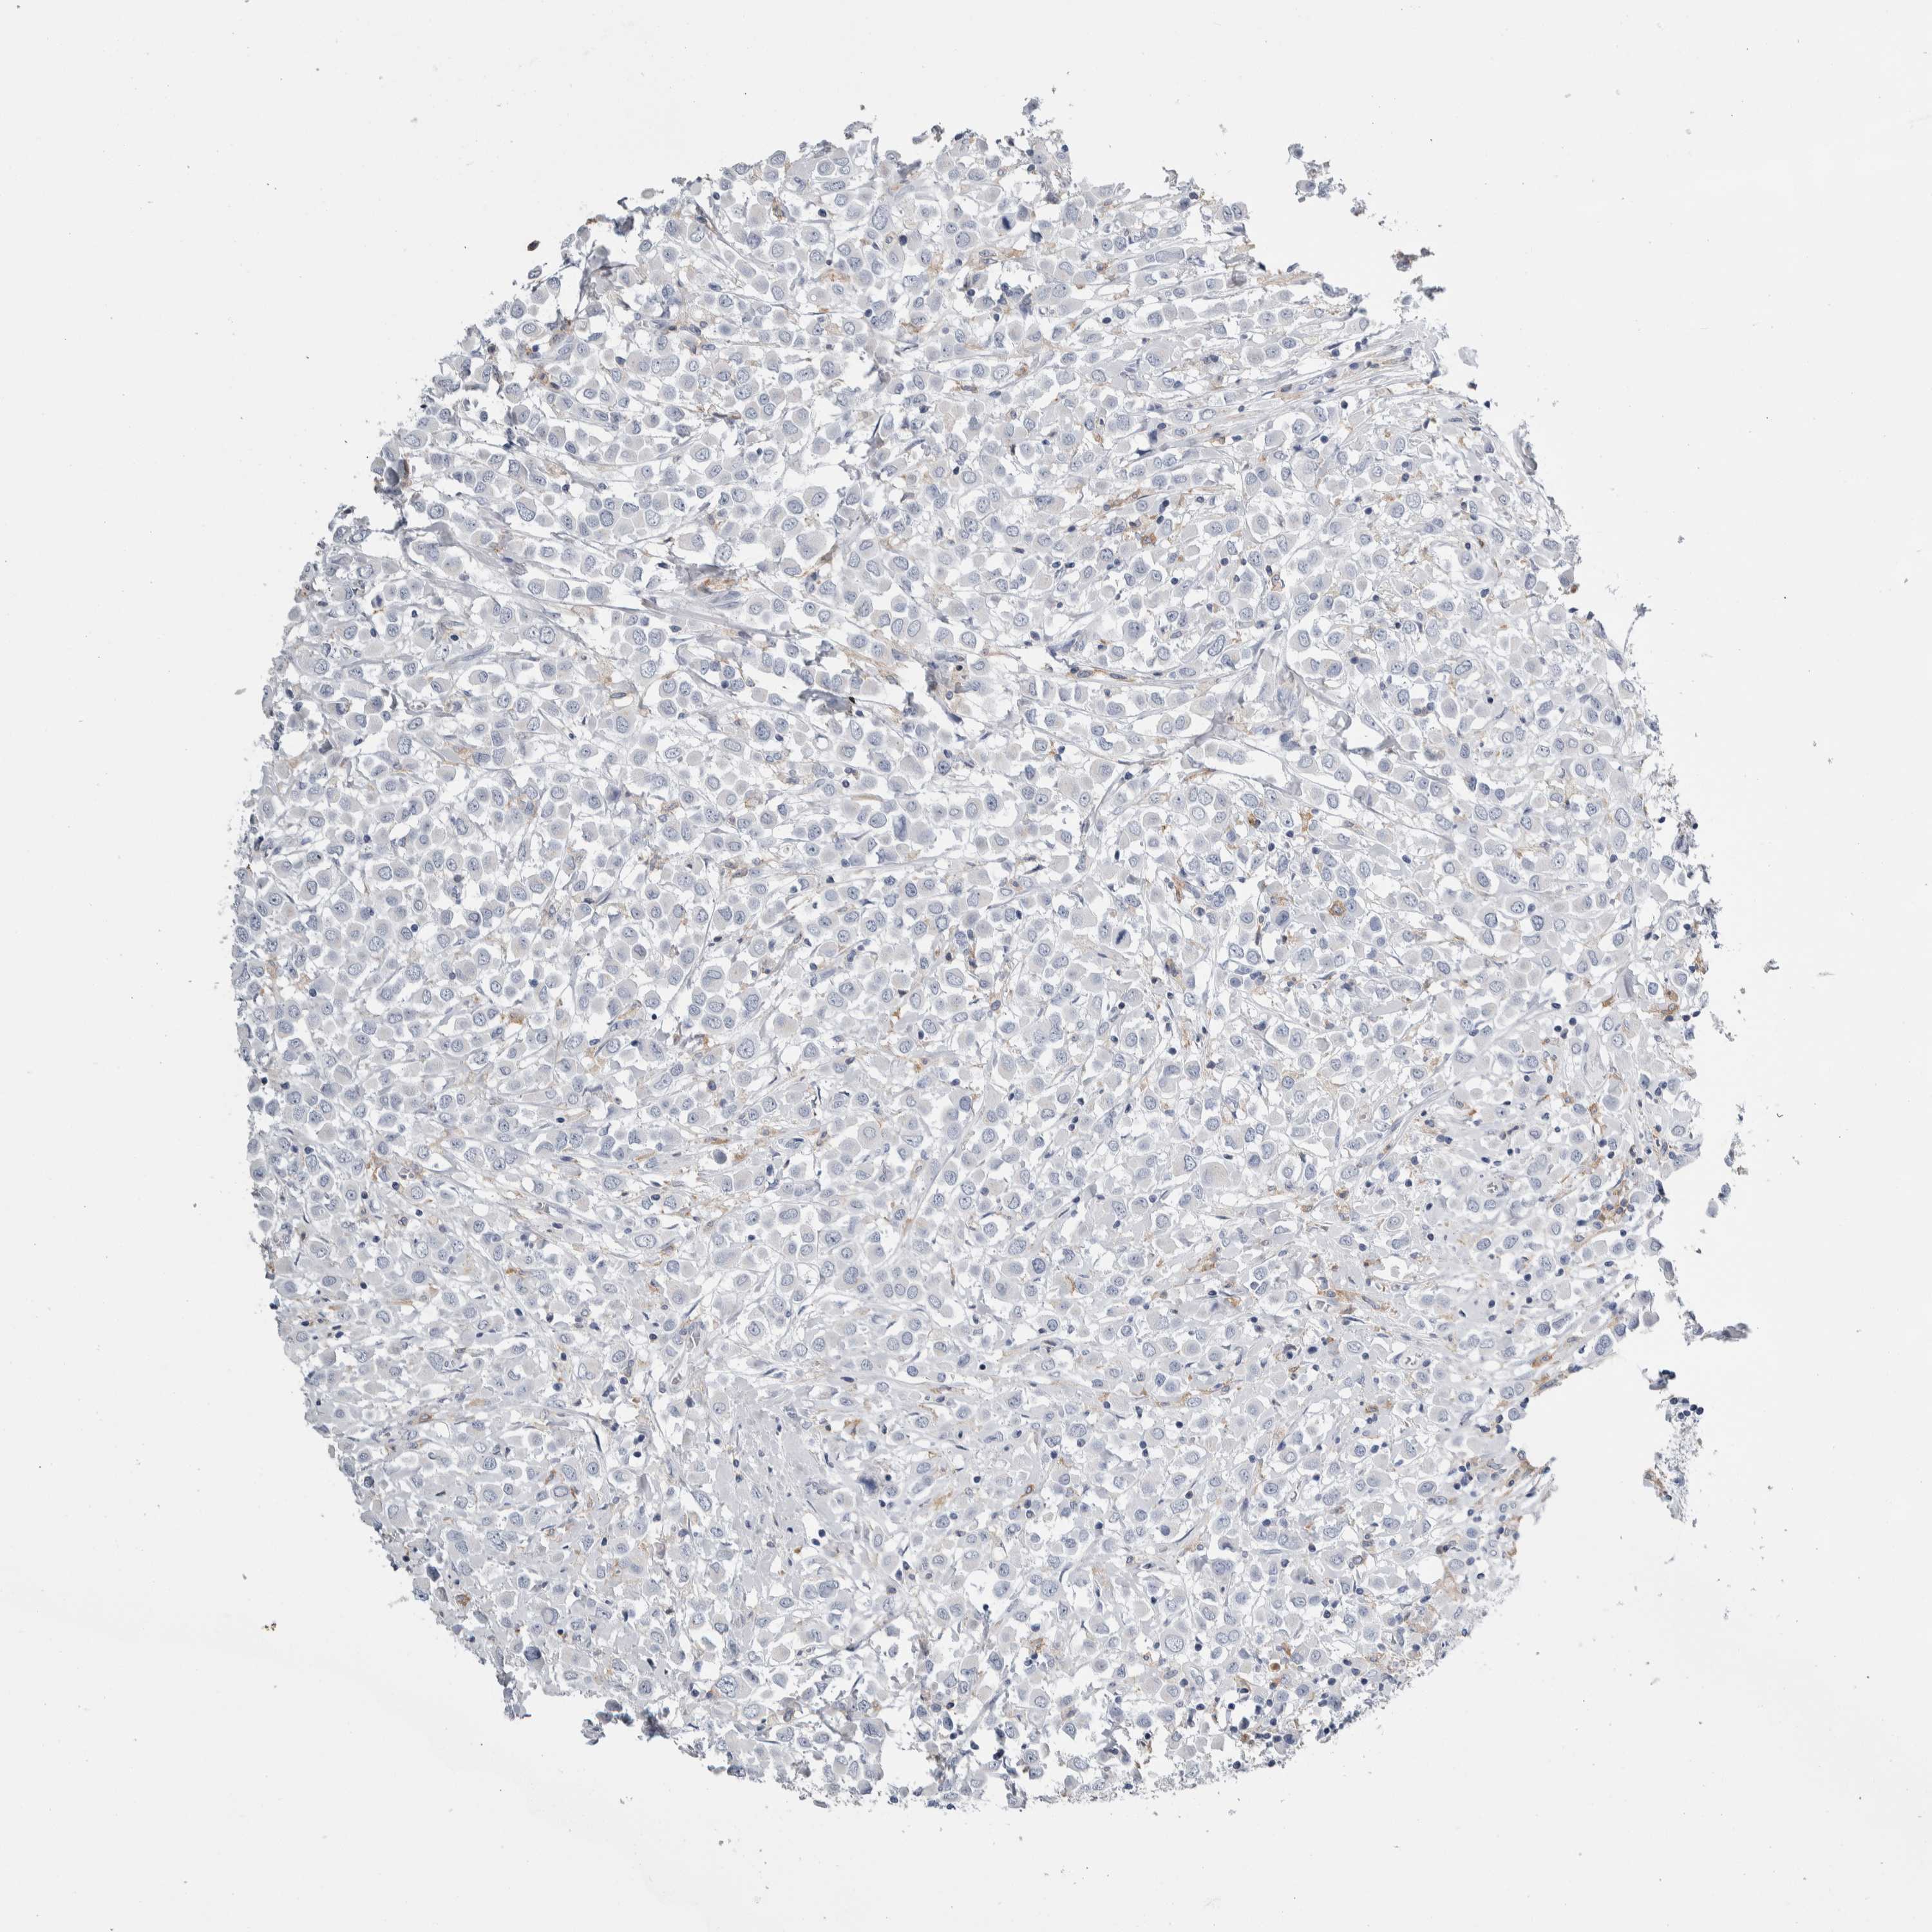

CANCER BREAST CANCER Show tissue menu

BRCA TCGA BRCA VALIDATION PROTEIN EXPRESSION